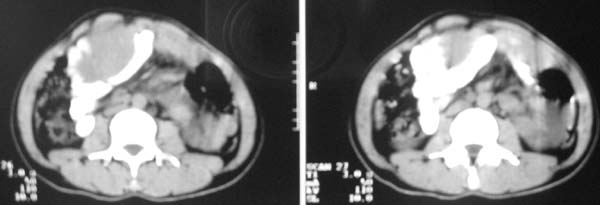

以下是引用老林在2007-9-27 22:11:00的发言:[br]肠系膜间质瘤可能大,建议增强

以下是引用zjzjr在2007-9-27 22:20:00的发言:[br]肠腔受推移,未见明显扩张及液平,所以考虑是肠外病灶, 间叶源性肿瘤?脂肪瘤?建议增强。

以下是引用余辉在2007-9-27 22:24:00的发言:[br]暂考虑肠道间质来源肿瘤如小肠平滑肌肉瘤/瘤可能,应该增强